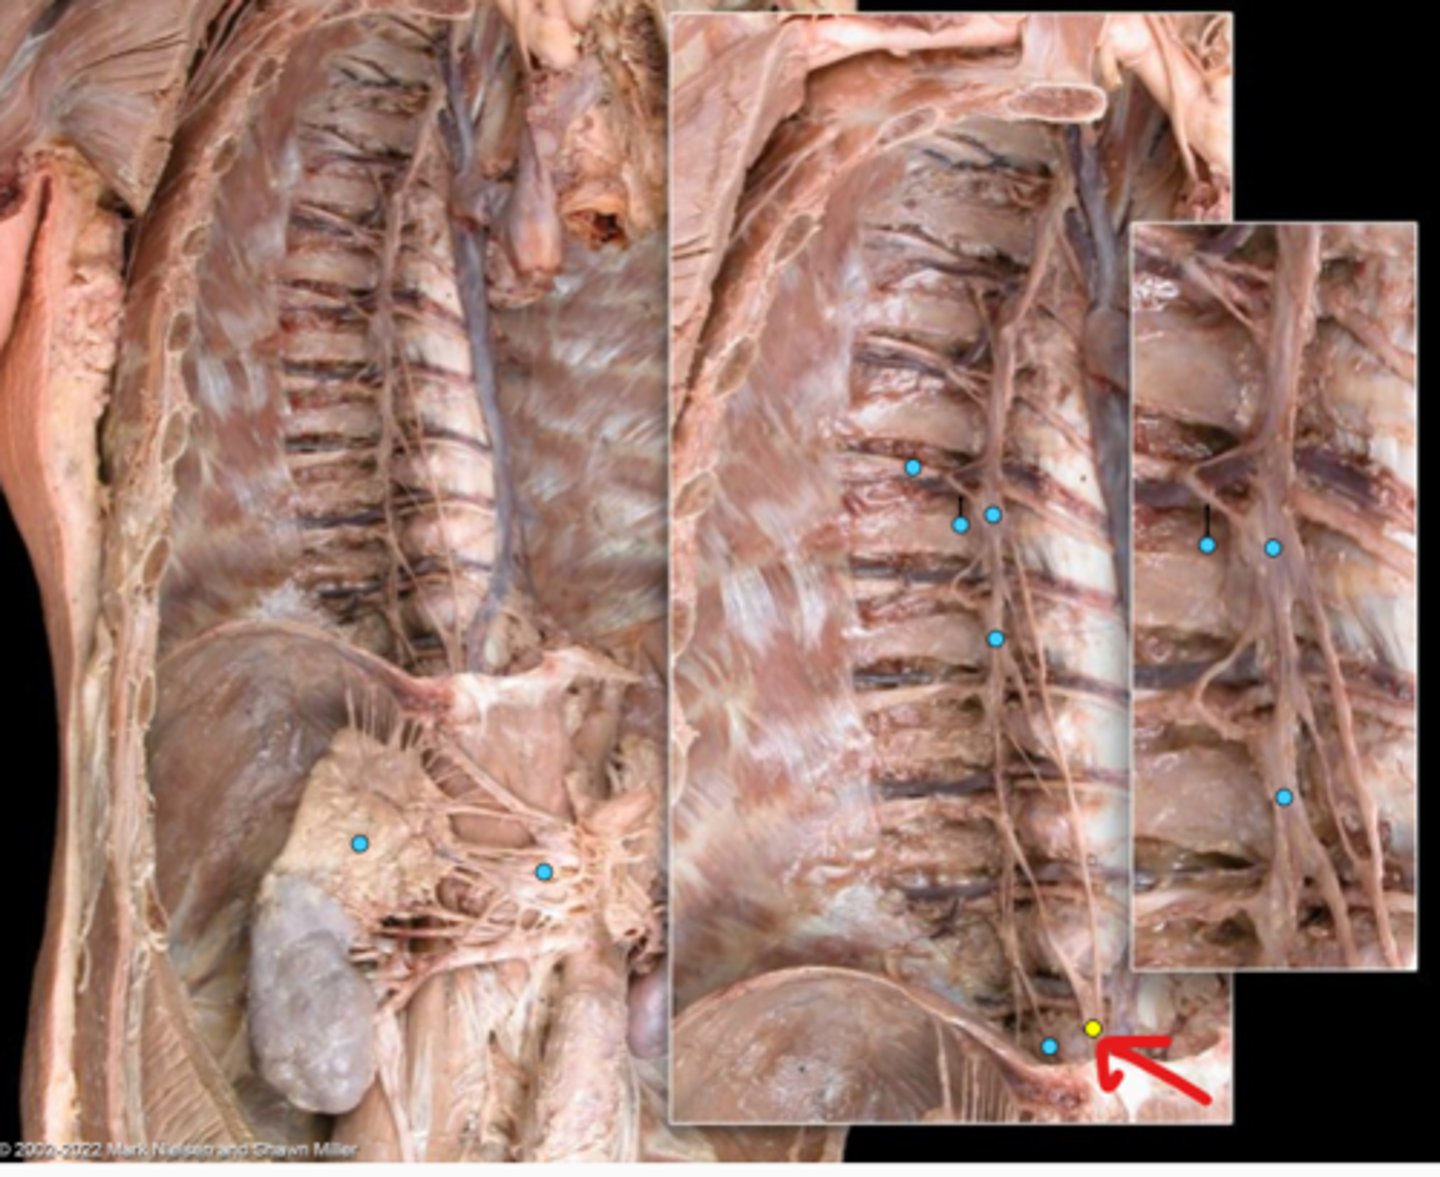

Suprarenal gland

Celiac ganglion

Intercostal nerve

Communicating ramus

Sympathetic trunk ganglion

Sympathetic trunk

Lesser splanchnic nerves

Greater splanchnic nerve

Anterior (ventral) ramus

Spinal nerve trunk

Posterior (dorsal) ramus

Spinal ganglion